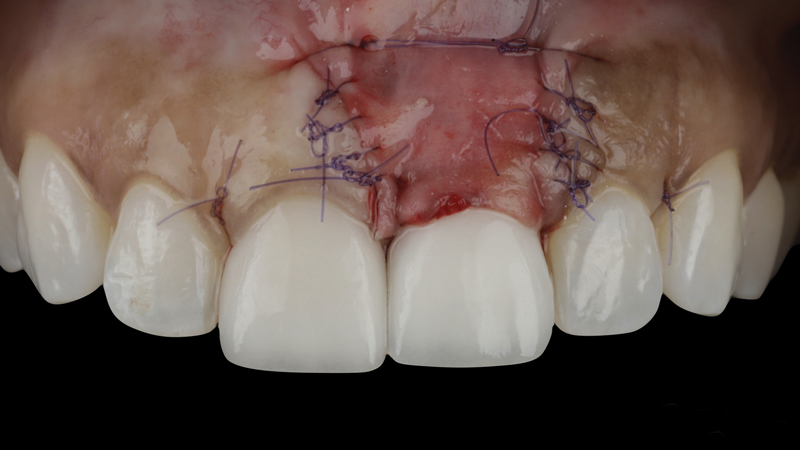

(15.) The flap was advanced and tension-free closure was achieved.

Figure 15